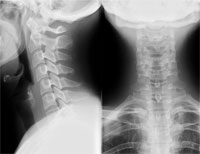

Le rachis cervical est particulièrement exposé dans les Lancers, de par :

- son anatomie assez singulière :

* présence d'un uncus au niveau de son plateau vertébral supérieur, sorte de rail qui guide le mouvement inter-vertébral cervical

* apophyse épineuse bifide

* présence de l'artère vertébrale qui le traverse de part en part dans le canal (foramen) transversaire (images ci-dessous en vue frontale et en coupe)